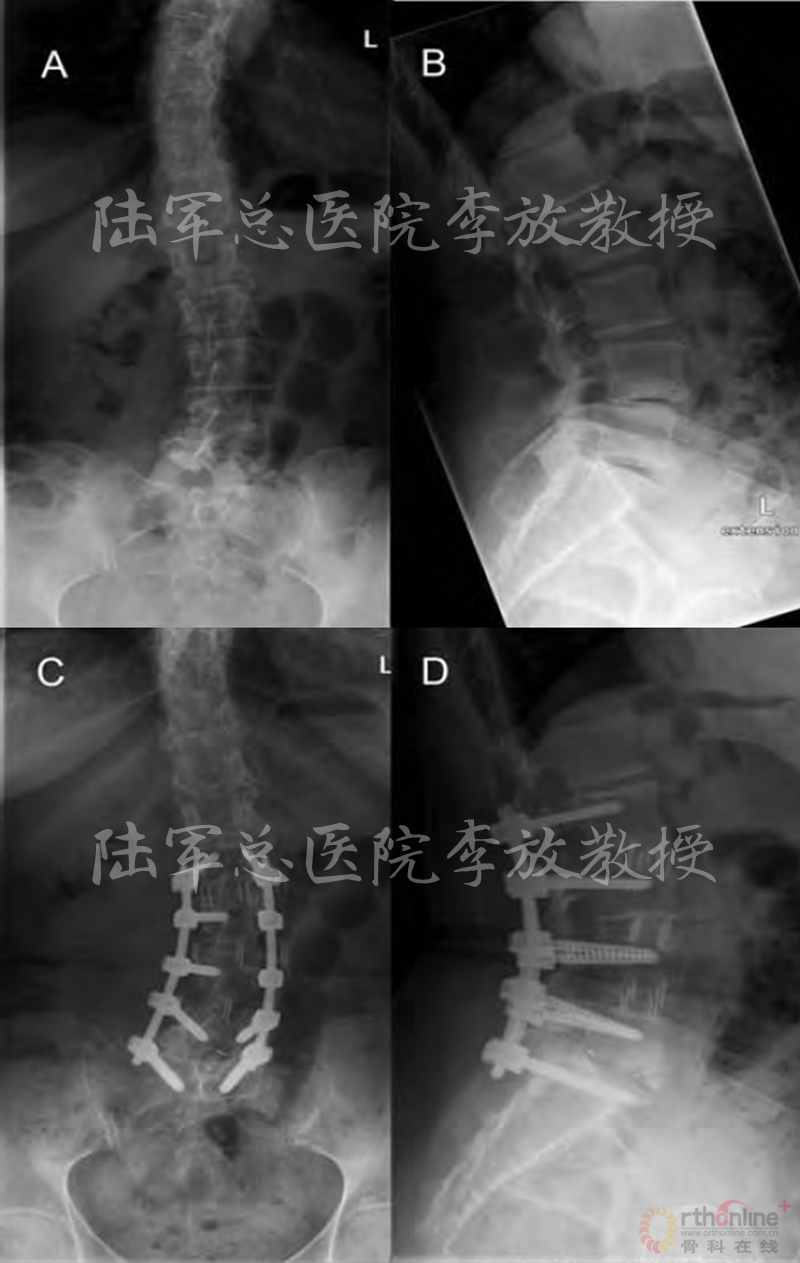

陆军总医院、全军骨科研究所李放教授分析了国内外相关研究,并结合临床经验得出结论:开放手术能够获得更好的矫形和减压效果;微创技术作为脊柱医生手中的新武器,对于一部分畸形较轻的病例,微创技术可以发挥其优势,但要严防特殊并发症;对于畸形严重的病例,微创手术处理存在困难,可谓开放能及微创所不及。他认为,开放和微创技术应该有机结合,重要的是如何去选择适应证,对不同的病例制订个体化方案。